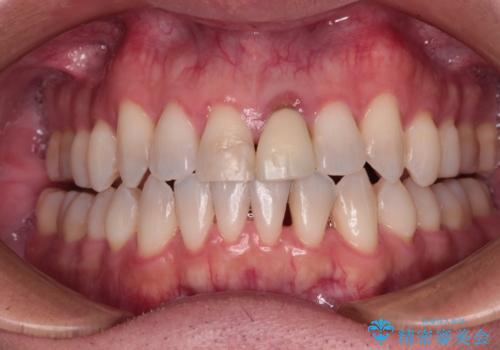

- 他院でインビザラインによる矯正治療を行っているものの、前歯の変色が気になるとのことで来院された患者様です。

インビザラインでの矯正治療がそろそろ終了とのことで、新しいインビザラインセットを発注する前に気になっている前歯2本をオールセラミッククラウンにて補綴治療を行うこととしました。

歯肉の腫脹が認められたため、仮歯へ置き換える過程で腫脹改善の指導などを行い、よりよい状態で治療を行うこととしました。

歯肉の腫脹は大分改善されましたが、なかなかご自身でのブラッシングが上達せず、やや腫脹残った状態での治療終了となりました。